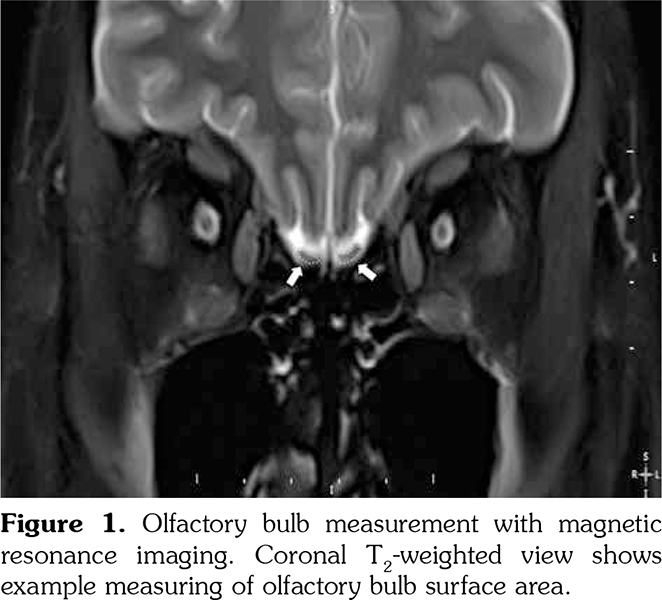

Olfactory bulb volumes were measured using cranial MRI examinations. Total OB volume refers to the sum of the right and left OB volumes. MRI evaluations were performed with a 1.5-T scanner (GE Healthcare’s Signa HDxt 1.5T MRI scanner, Waukesha, Wisconsin, USA). Images were gained with a protocol of 256x256 matrix and a 24-cm field of view, repetition time=5000 milliseconds (TR 5000 msec), echo time=130 milliseconds (TE 130 msec), number of excitations=2 (NEX 2) and a 5-mm slice thickness. OB volume was computed with the aid of the above images using three dimensional views. The volumetric evaluations were calculated by a 10-year experienced radiologist who was blinded to the subjects. An electronic cursor was used for manually delineating the contours of OB (Figure 1). The surface of the each slice area was calculated in mm2 and all surfaces were added and multiplied by front-back length to obtain a volume in mm3. Mean of the three consecutive measurements was taken into account. The observer established the minimum of the three consecutive measurements for measuring the MRI images. The intraobserver variability was determined at less than 5%.